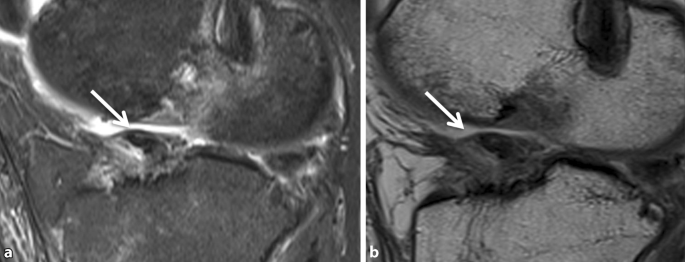

Partialrupturen können sich sowohl in einer Kaliberzunahme mit Signalintensitätserhöhung in T1- und T2-gewichteten Aufnahmen als auch in einer Ausdünnung der Sehne äußern (Abb. 7). Eine Elongation mit abgeflachtem Verlauf des Bands kann eines der Kriterien für die Partialruptur sein. Einer der Fallstricke für die Fehlinterpretation der Signaländerung ist die Synovialisation des Kreuzbandersatzes zwischen dem 3. und 12. postoperativen Monat. Die genaue Anamnese des Patienten mit der Information über den Zeitpunkt des Bandersatzes ist daher ausschlaggebend, um die Signalveränderung und Kaliberschwankung richtig einzuordnen.

Abb. 7

figure 7

Die sagittalen fettunterdrückten protonengewichteten Sequenzen zeigen eine deutliche Auftreibung und ein Ödem in der VKB(vorderes Kreuzband)-Plastik (Pfeil); eine komplette Diskontinuität liegt nicht vor. Eine Synovialisation kann ein ähnliches Erscheinungsbild erzeugen